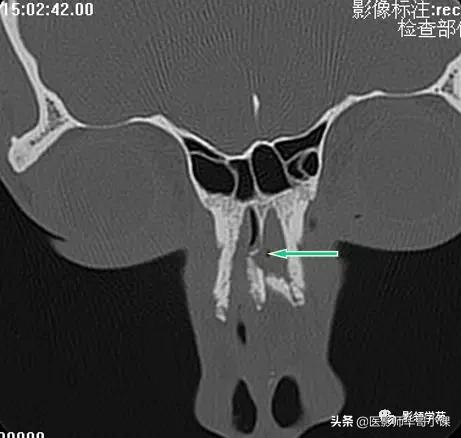

左侧鼻骨线形骨折

右侧鼻骨骨折

左上颌骨额突骨折